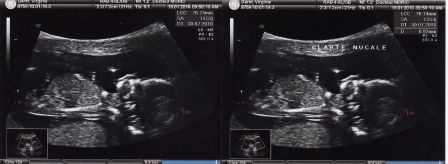

Bébé à 3 mois de grossesse

Par Virginie et Julien Garet le samedi, mai 15 2010, 20:59 - Avant la naissance - Lien permanent